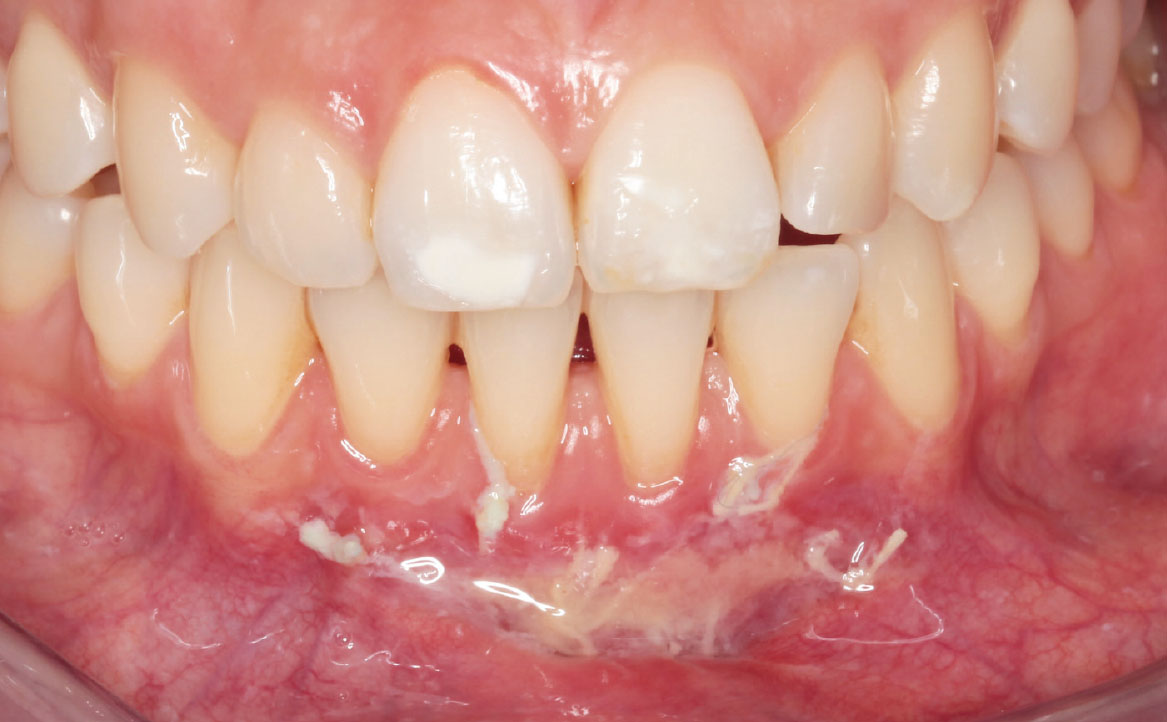

A una settimana dall’intervento si osserva un principio di guarigione della ferita: il sito appare completamente rivestito di fibrina e privo di segni di infiammazione (fig. 11, 12).

Al follow-up a un mese dalla vestibuloplastica, si osserva la completa riepitelizzazione del sito chirurgico (fig. 13, 14). Si riscontra la presenza di una piccola area esofitica, dovuta al mancato riassorbimento di uno dei punti di sutura applicati.